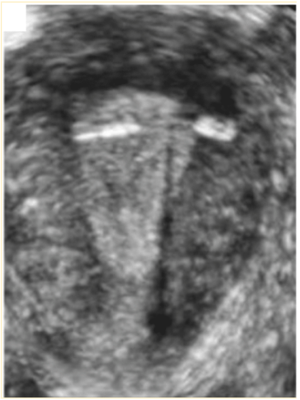

Paciente de 22 anos, teve inserção de DIU em consultório no quinto dia do ciclo. Minutos após a colocação, a paciente evoluiu com tontura, sudorese, bradicardia e cólicas intensas. A maioria dos sintomas melhoraram com repouso na primeira hora subsequente, exceto as cólicas. Nesse contexto, realizou-se ultrassonografia transvaginal, conforme imagem abaixo.

Qual é a conduta mais adequada?